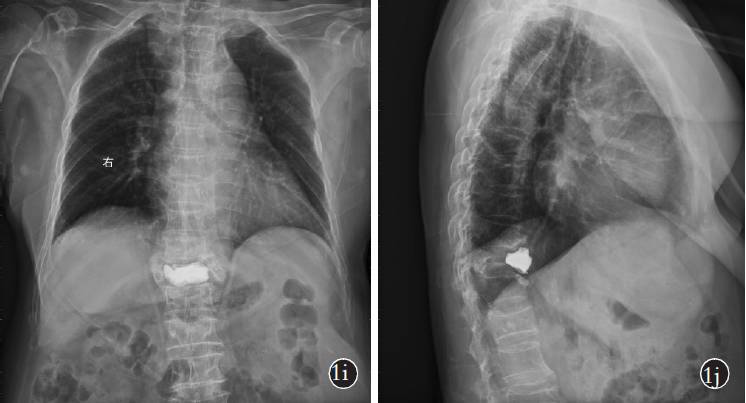

胸椎正侧位x片

术后3 年胸椎正侧位x 线片示骨水泥向前移位加重